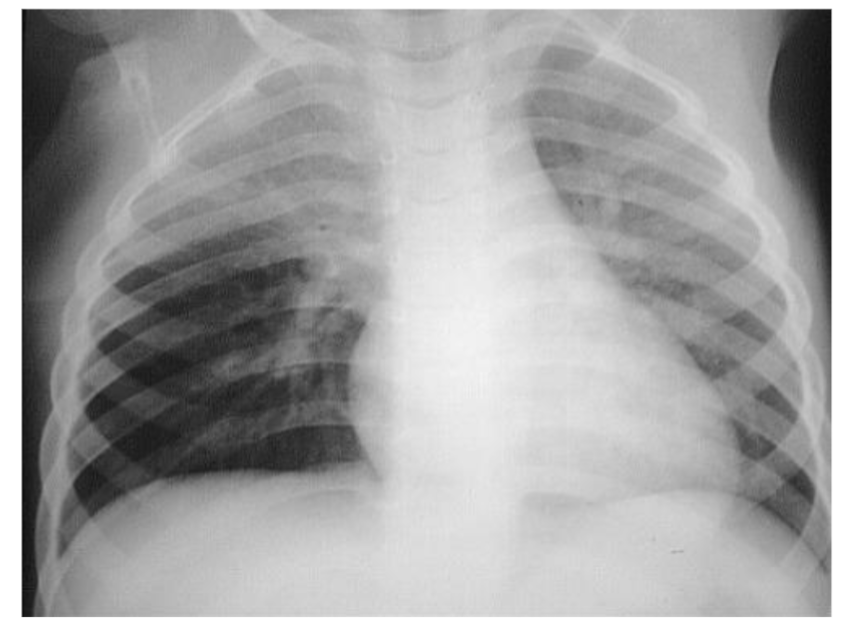

- AP chest film which shows complete opacification of the whole right lung - (1 .with shifted mediastinum and trachea to the left side

- .This indicates pleural effusion (PE) - (2

- After inserting chest tube, pus was coming out. This means that the PE is - (3 .an Empyema

- .The cause of this empyema is most likely a Bacterial Pneumonia - (4

- The age of the patient is 10 years which means that the most likely - (5 .organism is Streptococcus Pneumonae